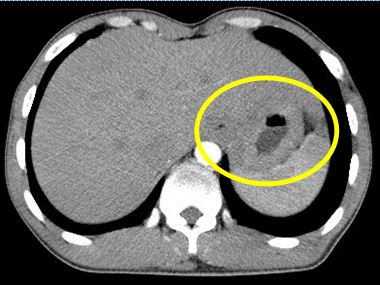

- Chụp CT bụng: U tâm vị dạ dày KT 35x48x52mm thâm nhiễm tổ chức xung quanh, hạch bờ cong nhỏ dạ dày KT 14mm.

Hình 2: Hình ảnh khối u tâm vị dạ dày có thâm nhiễm tổ chức xung quanh